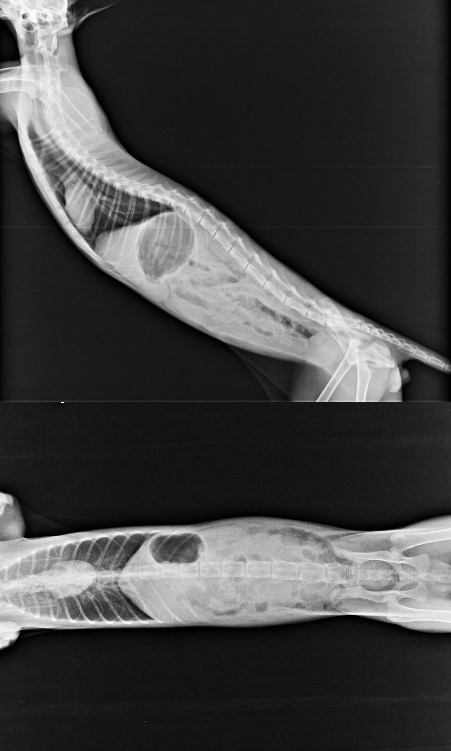

出院後回診,血檢白血球2萬9,肝指數偏高,有點脫水,超音波檢查小腸蠕動很快,大腸動很慢,x光片無明顯異常,上點滴給予抗生素治前三天數值緩緩的下降,第七天數值又開始攀升,改給與二線抗生素和少量類固醇狀況稍為穩定,精神和食慾尚可,逢年節在小賓狀況穩定後,已先出院回安養之家。

醫師覺得小賓尚幼有可能是肝臟發育未完全,也許長大會慢慢改善,或是年紀越長狀況會越明顯,或以下三種疾病

1.過敏性腸炎,自體免疫所引起的發炎性疾病

2.肝門脈分流

3.冠狀病毒

2/10 WBC 29000、ALT 271 AST 124 BUN 48

2/11 WBC 18700、ALT 207 AST 113

2/12 ALT 199 AST 111

2/14 WBC 24400、ALT 254 AST 157

2/16 WBC 20900、ALT 318 AST 185

2/17 ALT 284 AST 131

104.2.10-2.17住院醫療費用20259元

104.2.3門診血檢、糞檢、口服消化酵素、口服抗生素、B12及葉酸濃度檢測2511元

104.2.24門診血檢.驅蟲藥.口服藥2295元

共計醫療費用25065元